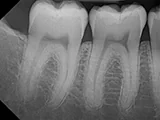

| X-Ray Example |

X-ray taken with the Dream Sensor |

Dental X-Ray Comparison

X-ray taken with the DentiMax sensorOpen Sensor

X-ray taken with the Caresream® sensorDexis